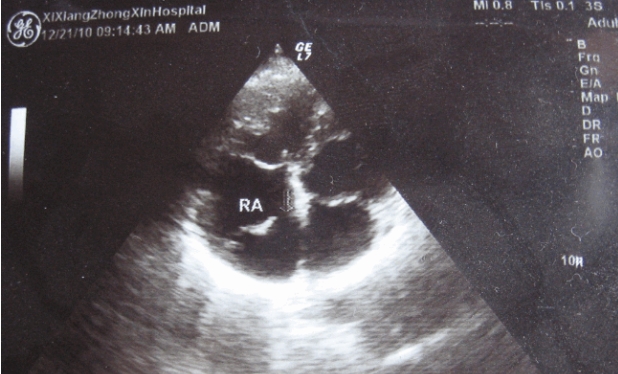

彩超是一种利用超声波进行无创检测的医疗技术,其原理是通过超声波在人体内部产生回声,然后利用电子学技术将这些回声转化为图像。通过颜色变化来反映不同组织或血流的速度和方向,从而帮助医生进行诊断。彩超其实并不是单纯的黑白图像,而是由各种灰度值构成的。在彩超中,不同的灰度值代表了不同的声强信号,也就是不同的回声强度,而这些回声强度的差异则反映了人体内部组织的密度、形态等特征。

这也就是彩超中Color Doppler技术的实现原理,通过对超声波信号进行多普勒频移分析,即将回声信号中因血液流动而引起的频率变化(多普勒效应)提取出来,从而反映出血液的流速和流向,并将其在图像上以不同颜色的形式呈现出来。